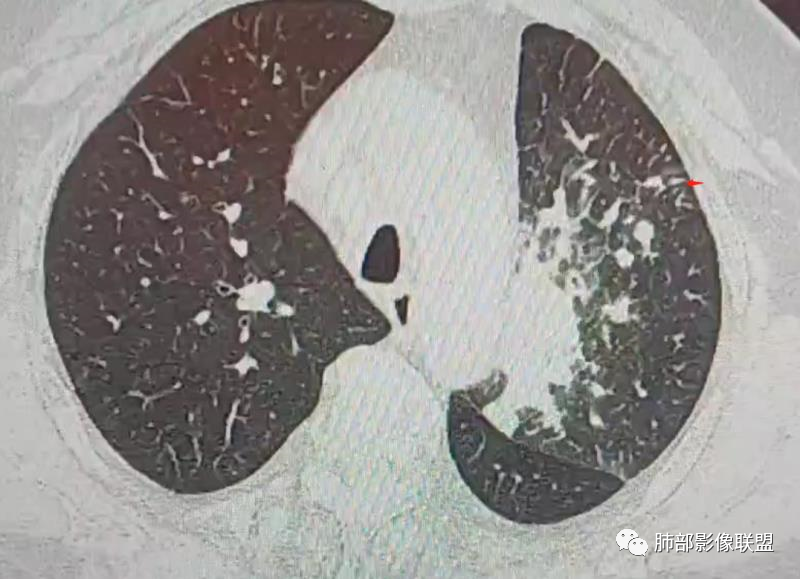

三、影像表现:左肺上叶多发片状高密度影,散在,边缘模糊,支气管壁稍增厚,中轴间质、小叶间隔增厚、有结节感,左肺上叶前段病灶可见胸膜增厚,部分小支气管不能分辨;右肺上叶后段混合磨玻璃结节,边界清,邻近胸膜凹陷;纵膈淋巴结肿大;心包增厚;左侧少量胸水。此外,扫及右侧胸腔内甲状腺肿;左侧肩胛骨旁肌群内脂肪瘤。

四、综合分析:老年男性,以咳嗽咳痰为主要临床表现,无发热,白细胞正常,影像表现为左肺上叶片影,前段结节影、胸膜增厚、部分小支气管不能分辨。左肺上叶中轴间质增厚、小叶间隔增厚、结节感,肺门纵隔见肿大淋巴结,尽管肺部病病灶边缘特征不典型,但高度疑及癌性淋巴管炎这一“次生灾害”却具有相当重要提示意义,而肺癌中最常伴癌淋的就包括腺癌。右肺上叶后段混合磨玻璃结节,边界清楚,张力明显,具有一定特征性,高度指向浸润性腺癌。这对于左肺病灶具有一定程度“助攻”效应。总体而言,本例左肺病灶的诊断关键点在于判断出癌性淋巴管炎。癌性淋巴管炎的结节在外围间质多见,小叶间隔可呈串珠状、结节状增厚,由于出血及水肿,小叶间隔增厚较明显,或呈不规则增厚。有的肺小叶呈多角状阵列。常合并胸水。